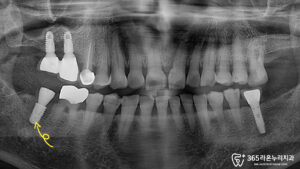

정밀 검사 결과, 오른쪽 아래 어금니(47번 치아) 주변으로 뼈가 많이 소실된 상태였습니다.

치아 뿌리 아래쪽까지 염증이 진행되어 더 이상 살리기 어려운 상황이었죠.

이번 환자분의 경우, 전신 건강 상태가 양호하고 잇몸 상태도 치료가 가능한 수준이었기 때문에 발치와 동시에 임플란트를 식립하는 ‘즉시 임플란트 식립’ 방법을 선택했습니다.

치근단 주위염증이 발견된 부위인 사랑니 포함, 2개의 어금니를 발치한 후, 발치 자리에 바로 임플란트를 심고 뼈 이식까지 함께 진행했습니다.

충분한 치유 기간이 지난 후 정밀한 수치 측정을 통해 임플란트의 안정성을 확인했습니다.

다행히 임플란트가 뼈와 잘 결합되어 있었고, 이식한 뼈도 성공적으로 자리 잡았음을 확인할 수 있었습니다.